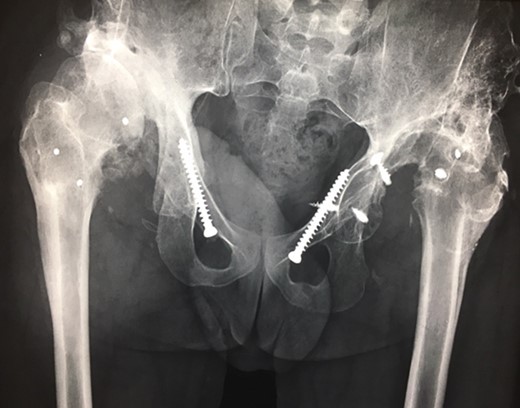

Ten years ago, a 12-year-old male presented to our clinic complaining about limping and massive swelling of the left hip. Figure 1 shows the initial X-ray and the 3D reconstruction of the left hip at first presentation when the femoral head, had already destroyed the lateral edge of the acetabulum like a mortar. Severe pain episodes have apparently not been noticed and a former hip dysplasia was not known. A brief clinical history revealed that the patient presented repeated episodes of finger biting and fevers from 2 to 8 years old. The intelligence level of the patient was at an average. The patient was admitted to a paediatric neurologist and a genetic test. A mutation of the NTRK1 gene was found and the diagnosis of CIPA was established. The right hip initially appeared to be normal and the patient was walking, therefore surgical reconstruction for the left hip was proposed due to massive swelling, inability of normal walking and significant limb length discrepancy. A Tönnis/Kalchschmidt triple pelvic osteotomy with open reduction and a shortening varus derotation osteotomy (VDRO) of the femur was performed (Fig. 2A–B). After 3 months the patient was walking again but another 3 months later the hip dislocated again without severe pain. Although the femoral head was already damaged the hip joint was reconstructed again by open reduction, capsular reconstruction with suture anchors and a trevira tube and a movable external fixator was used to temporary stabilize the joint (Fig. 3). The right hip at this time was still intact and was protected with a pneumatic orthotic device. A few months later in 2009, despite all surgeries, the left hip had entirely lost congruency and the right hip developed subluxation despite conservative treatment (Fig. 4). The patient was still walking so the decision to reconstruct the right hip with open reduction, capsular augmentation with a trevira tube, a triple pelvic osteotomy and VDRO was made (Fig. 5). Few months later this reconstruction failed as well and the hip dislocated without severe pain (Fig. 6).

(2008) Despite reconstruction the femoral head subluxated and rapidly lost congruency. An open reduction and capsular reconstruction with trevira tube, removal of the femoral plate and temporary fixation with an external fixator with movable hip mechanism for flexion of the joint (Orthofix MonoRail) was performed.